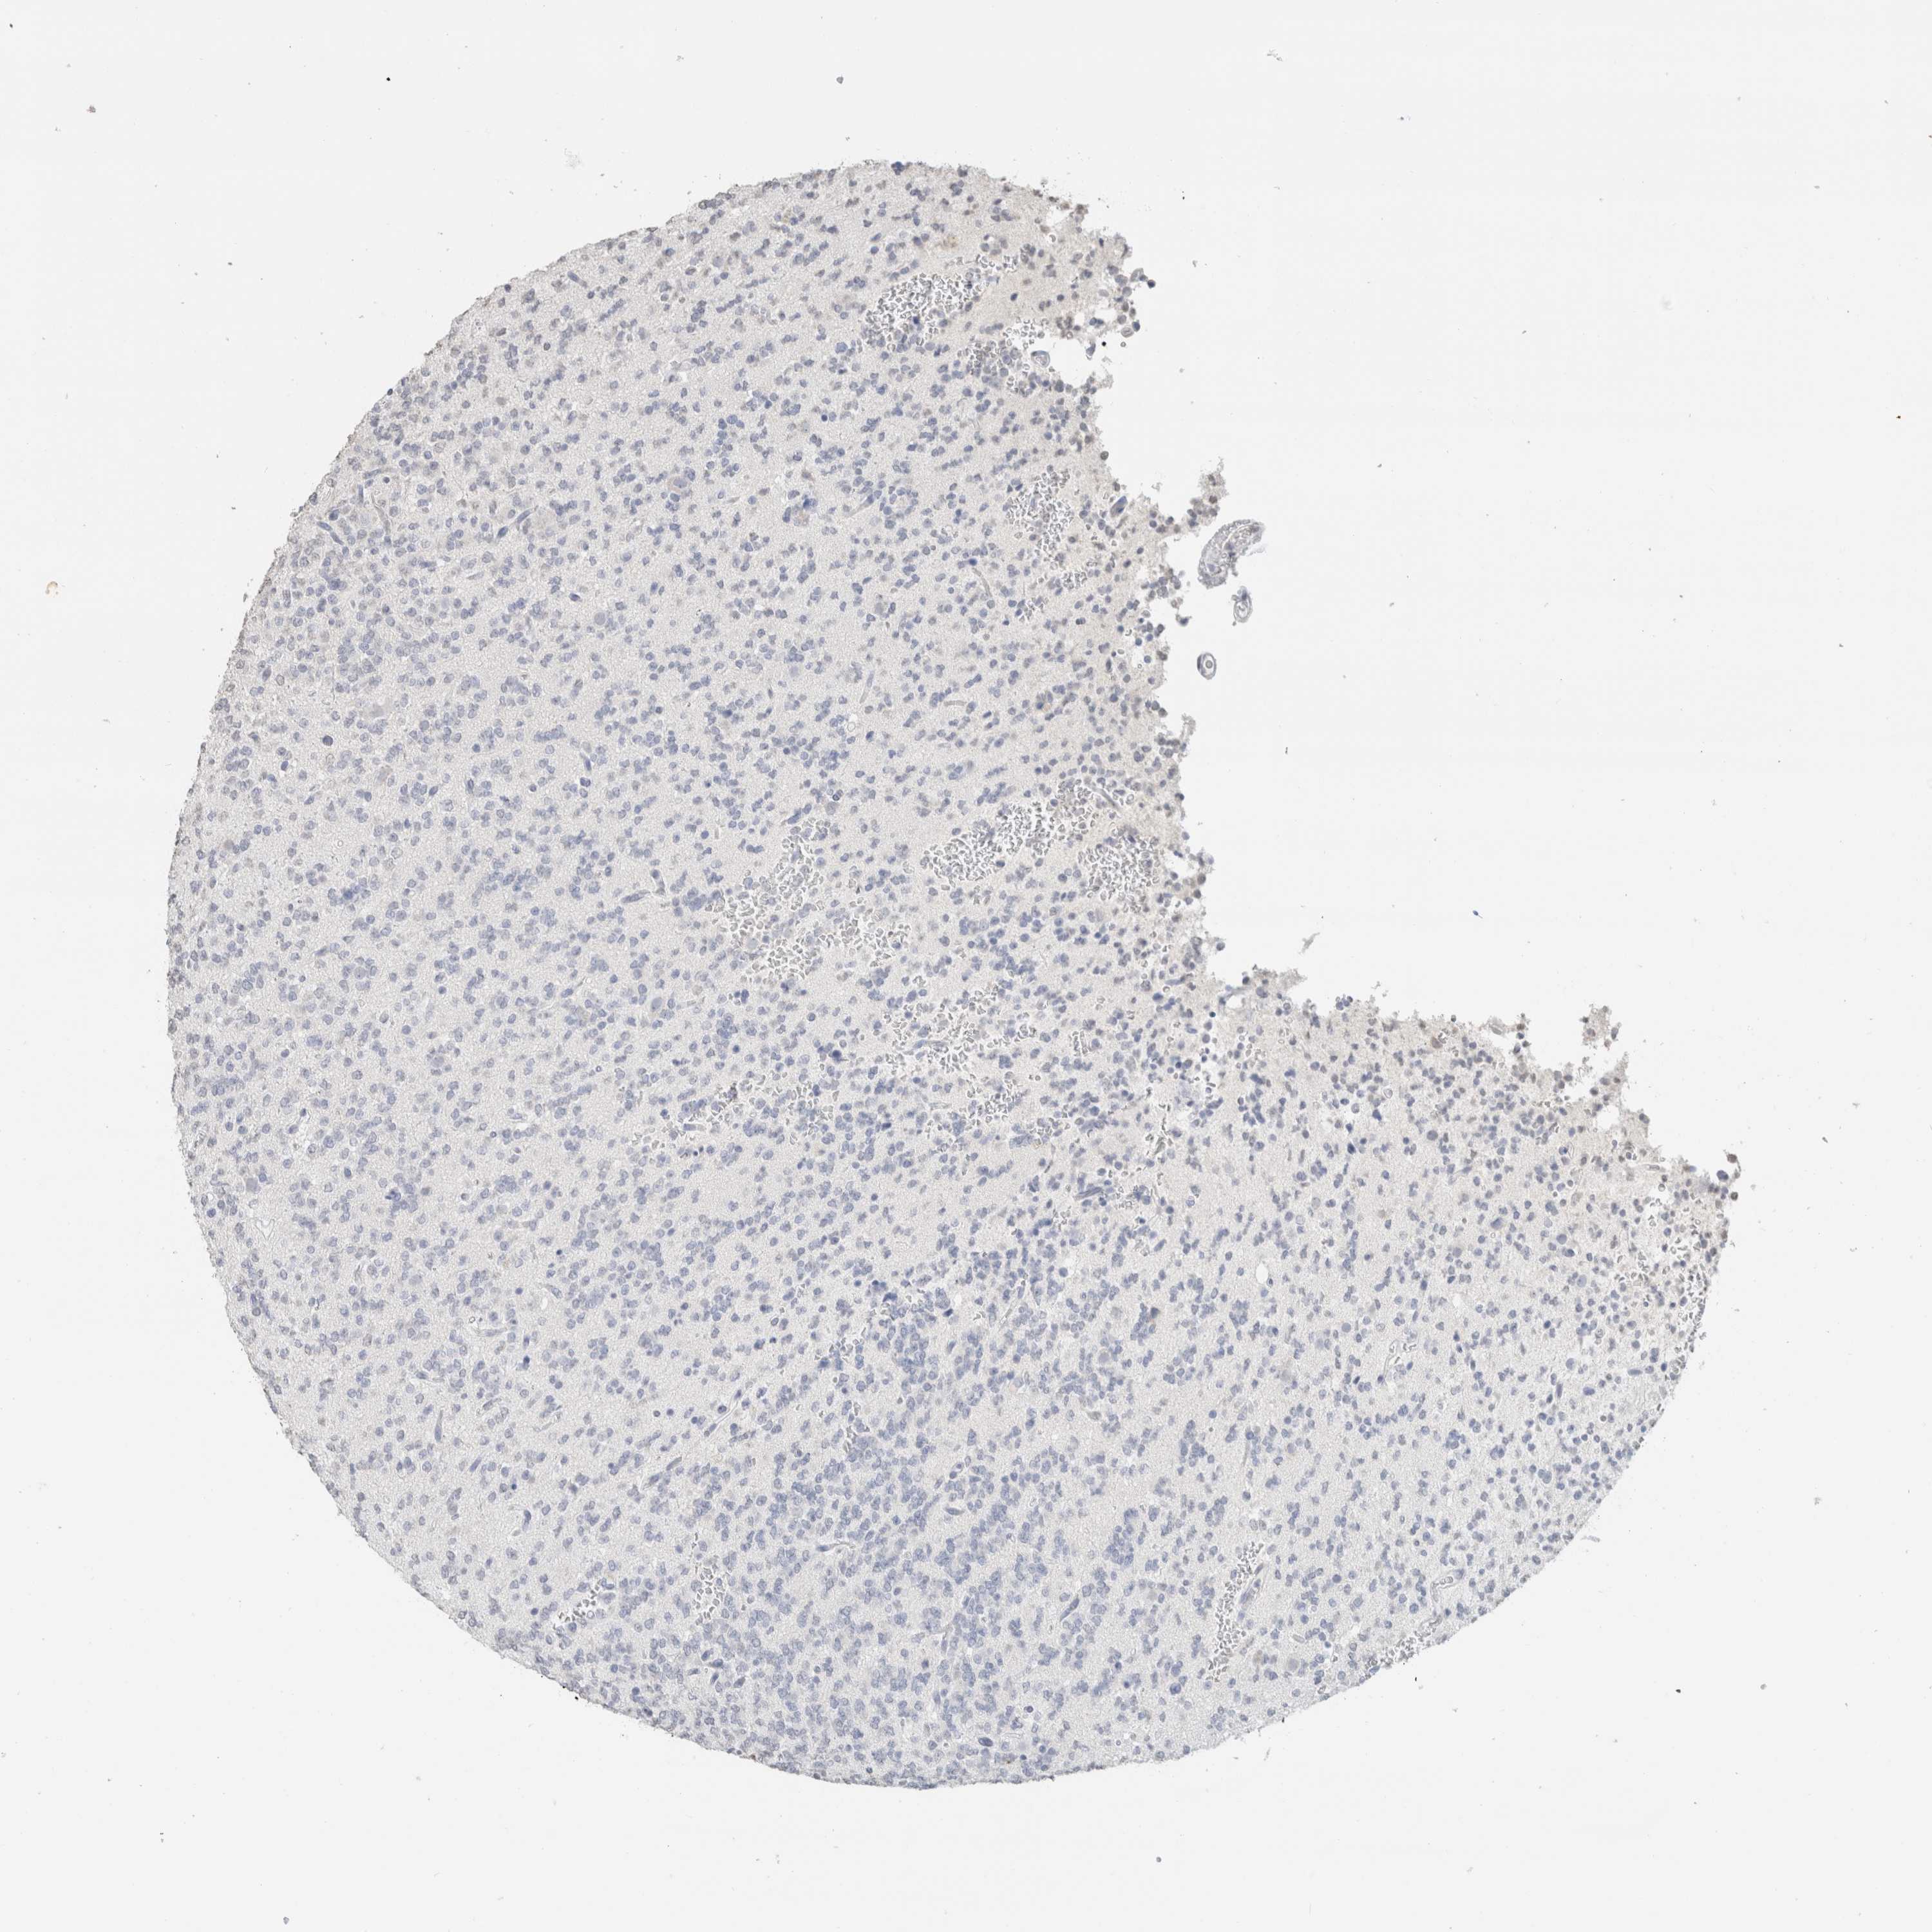

GLIOMA - Protein expressioni

A mouse-over function shows sample information and annotation data. Click on an image to view it in a full screen mode. Samples can be filtered based on level of antibody staining by selecting one or several of the following categories: high, medium, low and not detected. The assay and annotation is described here.

Note that samples used for immunohistochemistry by the Human Protein Atlas do not correspond to samples in the TCGA dataset.

Antibody stainingi

Antibody staining in the annotated cell types in the current human tissue is reported as not detected, low, medium, or high, based on conventional immunohistochemistry profiling in selected tissues. This score is based on the combination of the staining intensity and fraction of stained cells.

Each image is clickable and will lead to virtual microscopy that enables deeper exploration of all samples and also displays staining intensity scores, fraction scores and subcellular localization as well as patient and tissue information for each sample.

Antibody HPA050092

Antibody CAB025368

Glioma, malignant, High grade

Glioma, malignant, Low grade